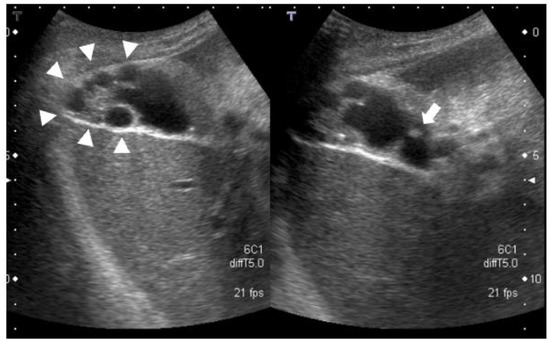

- Contrast-enhanced MRI: there was a 4-mm gallbladder body polyp and no abnormal signals in the thickened wall at the fundus of the gallbladder (Figure 3);